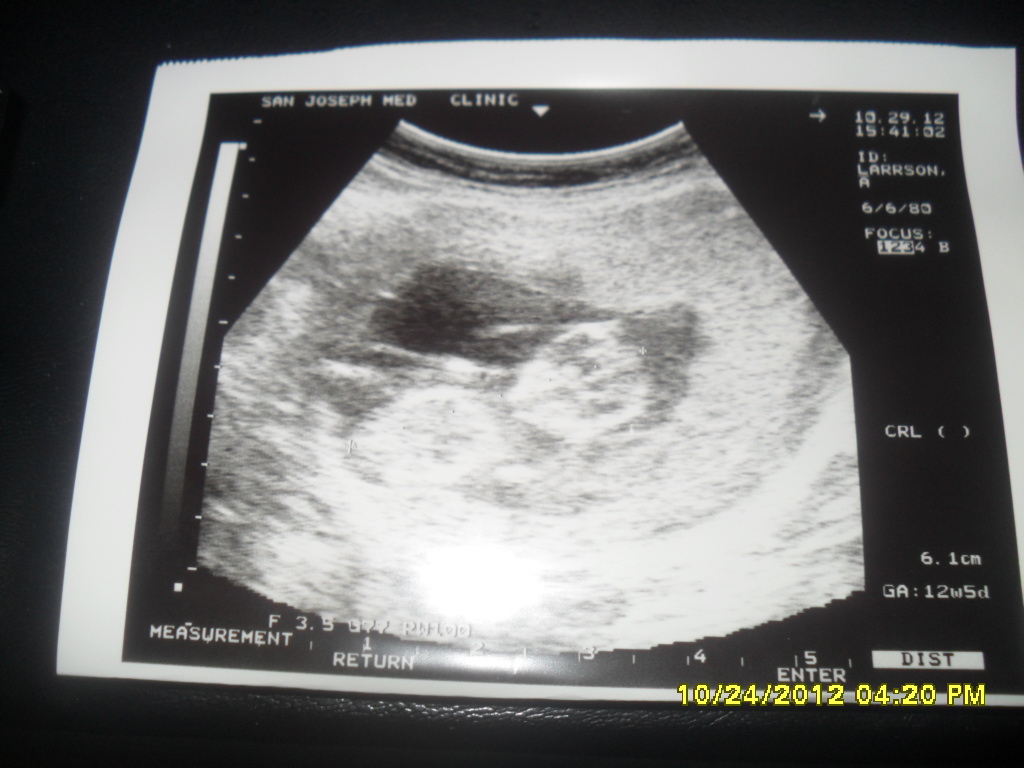

Such a horrible pic but if you could try to make out a guess it would be much appreciated! Cant see the nub area (Dr took the first image he saw) so Im thinking it looks like a Boy skull but again its really hard to tell and the quality is awful! :awe: was 169... Thank girls!!

Attachment 5770